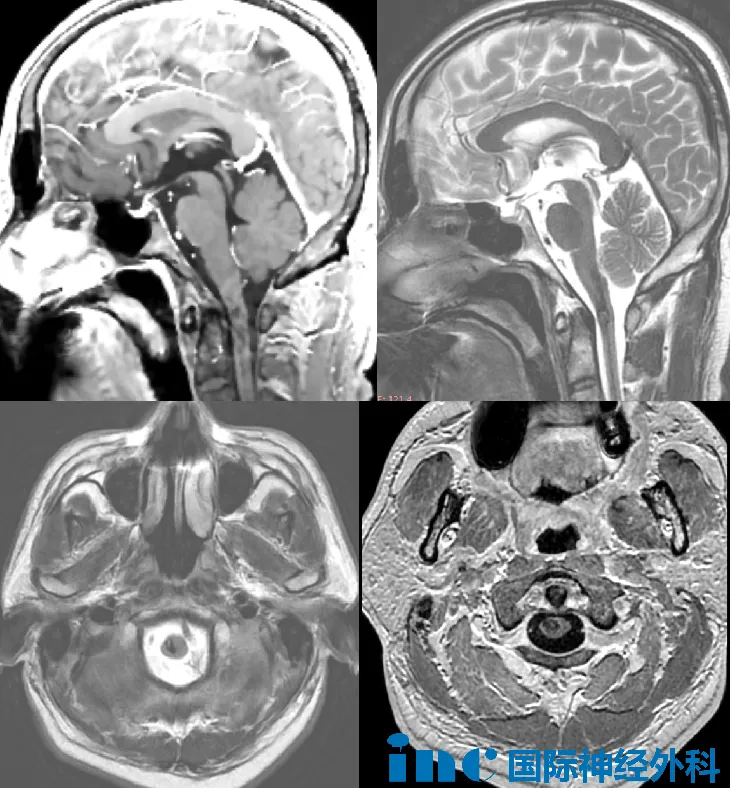

12月底的MRI检查带来了明确诊断,也带来了新的抉择:延髓区海绵状血管瘤。面对这个紧贴生命中枢的“不速之客”,多家医院都因手术风险太高建议保守治疗。

“影像显示了位于C1颈髓内的一个海绵状血管畸形此前导致了一次内生性出血,进而向上扩展到延髓下部。实际上,导致最初出血的根本原因是位于脊髓右侧的血管畸形。但手术切除技术上完全可行。我知道如何安全暴露病灶,虽然不是紧急手术,但结合你之前的出血情况,尽早切除才能避免后续风险。”